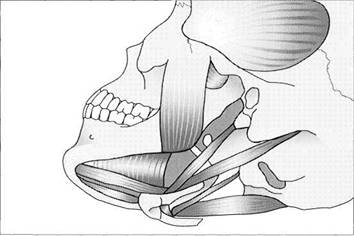

Muscles of mastication

Drawing of the muscles of mastication. In the narrowest sense these include only the temporal, masseter, medial pterygoid, and lateral pterygoid muscles. The suprahy-oidal musculature is also shown here because it is of interest in the diagnosis and treatment of functional disturbances. The sternocleidomastoid muscle is not included here because it belongs to the musculature of the neck.